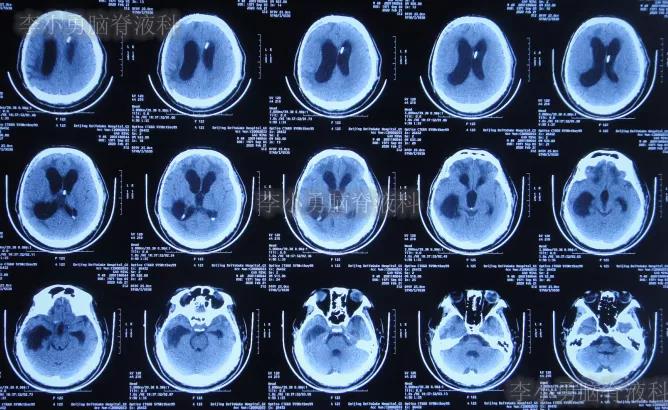

2018年8月17日(开颅术后37天),意识仍不清,查头颅CT示脑室扩张,脑膨出,有钙化(图-1);再次给予腰大池持续引流7天后拔除。

图-1:2018年8月17日头颅CT

2018年8月28日(开颅术后48天),查头颅CT示脑室进一步扩张,脑膨出加重(图-2);但意识还可以,未给予继续治疗。

图-2:2018年8月28日头颅CT